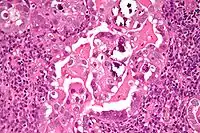

| Micrograph of uterine serous papillary carcinoma. H&E stain. | |

Histopathologically, uterine serous carcinomas is typically characterized by (1) nipple-shaped structures (papillae) with fibrovascular cores (2) marked nuclear atypia (irregularies in the nuclear membrane, enlarged nuclear size), (3) psammoma bodies and (4) cilia.